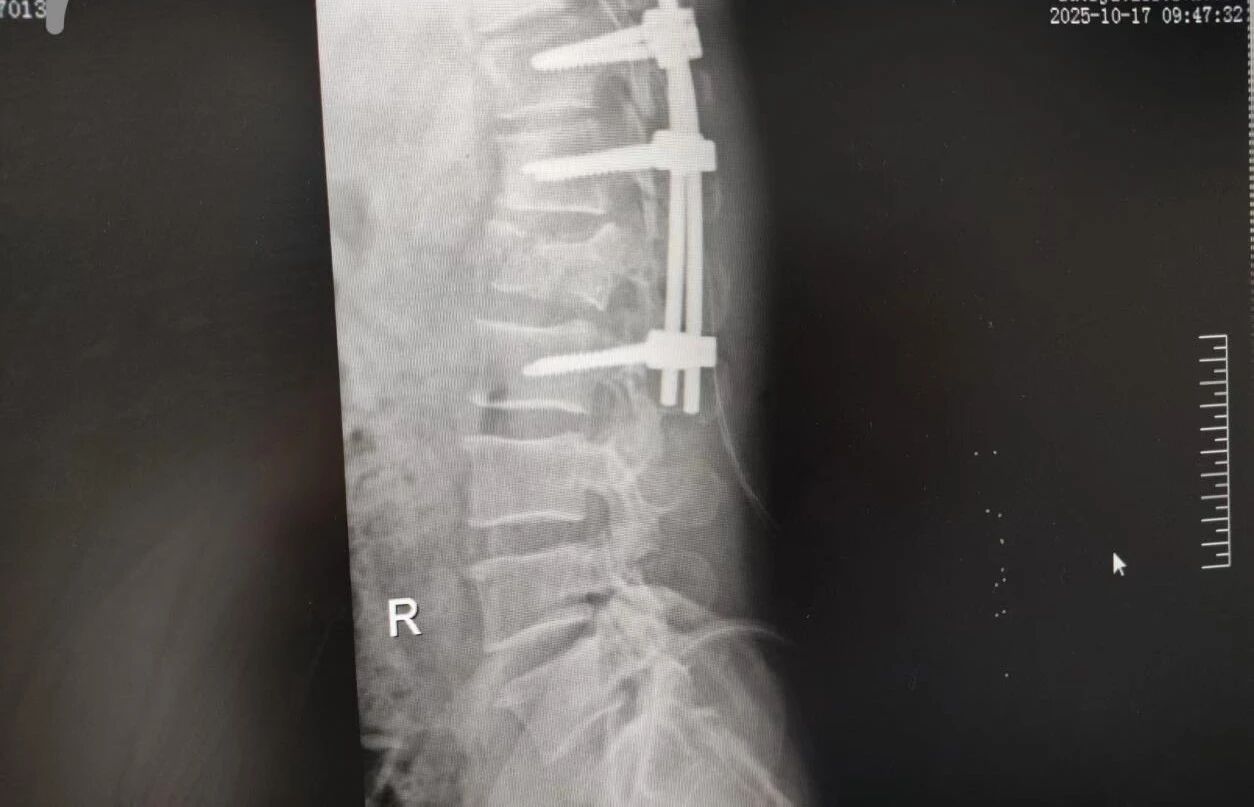

63 歲的王先生(化名)高空作業(yè)時不慎墜落,由漯河市中醫(yī)院急診科緊急接診。入院時,他已生命垂危,初步檢查結(jié)果觸目驚心:腰 1 椎爆裂性骨折(脊柱嚴(yán)重?fù)p傷,隨時面臨永久性癱瘓風(fēng)險)、多發(fā)肋骨骨折伴血?dú)庑嘏c肺挫傷(胸腔 “堡壘” 重創(chuàng),呼吸功能幾近崩潰)。任一傷情皆足以致命,多重重創(chuàng)更讓其陷入生死絕境。

針對腰椎傷情,骨科竇志剛醫(yī)生團(tuán)隊緊急開展腰 1 椎體爆裂性骨折切開復(fù)位內(nèi)固定術(shù) + 椎板切除減壓術(shù)。手術(shù)室、麻醉科無縫銜接開通綠色通道,手術(shù)團(tuán)隊快速就位,術(shù)后患者下肢活動恢復(fù)自如。